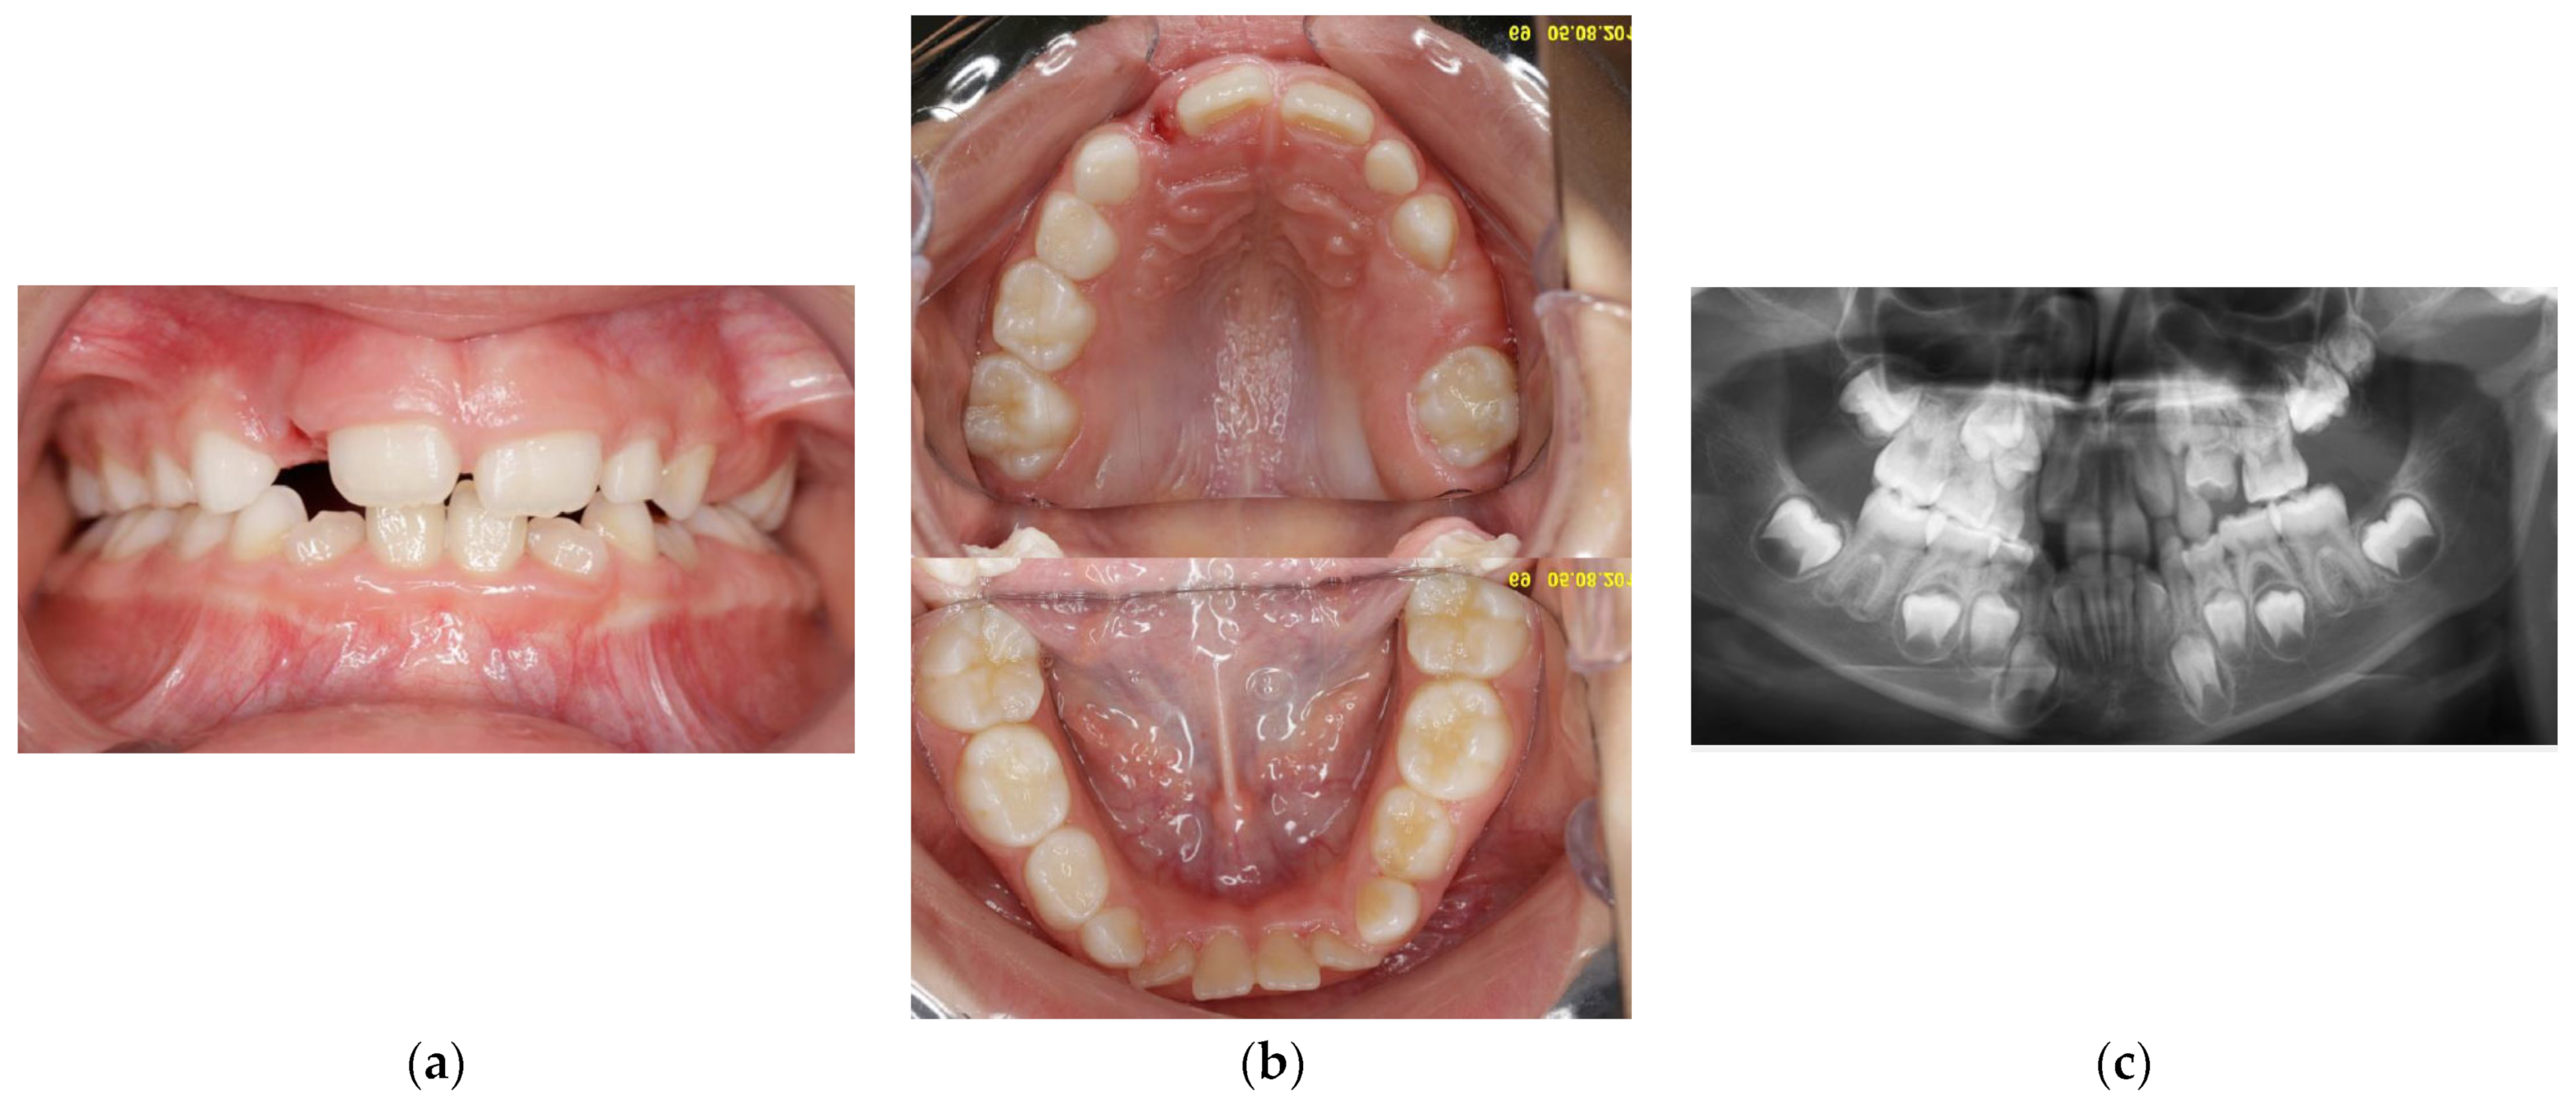

At the age of 12 y and 11 m, while the upper canines were erupting, the clinical and radiological situation in the distal part of the upper left quadrant was not much different from before (Figure 8a–c).

Figure 8.

Age of 12 y and 11 m. Intraoral pictures (a,b) and panoramic X-rays (c) showed retained 26 and 27.